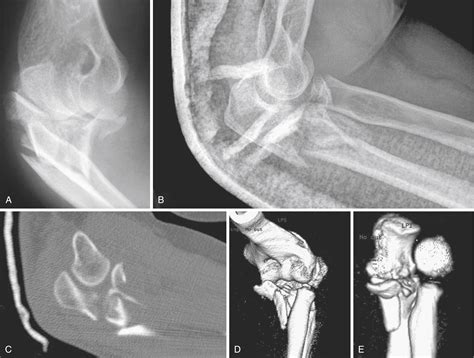

Understanding the opposite of proximal in anatomy is not just about memorizing terms; it's about grasping the spatial relationships within the body. This knowledge is vital for diagnosing and treating injuries and diseases. For instance, a distal fracture in the arm would be a break near the wrist, while a proximal fracture would be near the shoulder.

In medical applications, the opposite of proximal is particularly important. For example, in orthopedics, understanding the distal and proximal ends of bones is crucial for diagnosing and treating fractures. A distal fracture in the leg would be a break near the ankle, while a proximal fracture would be near the hip.

• Medicine: A distal fracture in the arm is a break near the wrist, while a proximal fracture is near the shoulder.